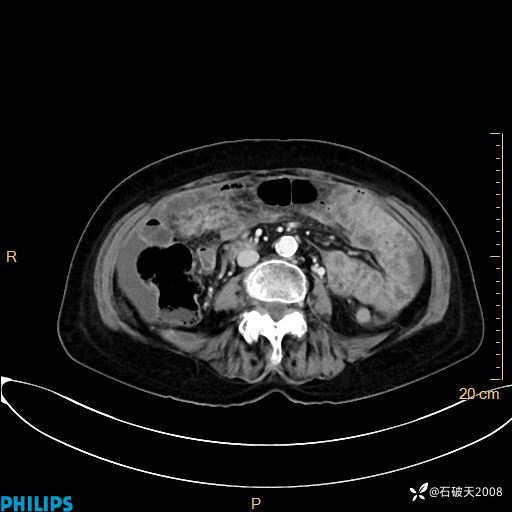

MIP